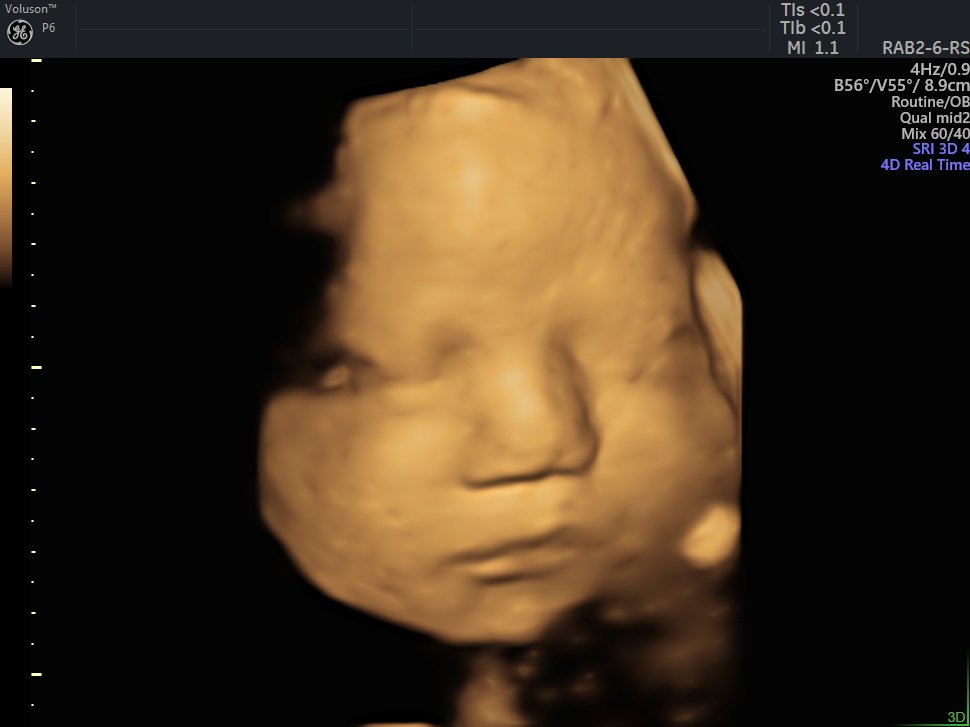

4 D Ultrasonografi

4 Boyutlu (Renkli) Ultrason ve Doppler Ultrasonografi